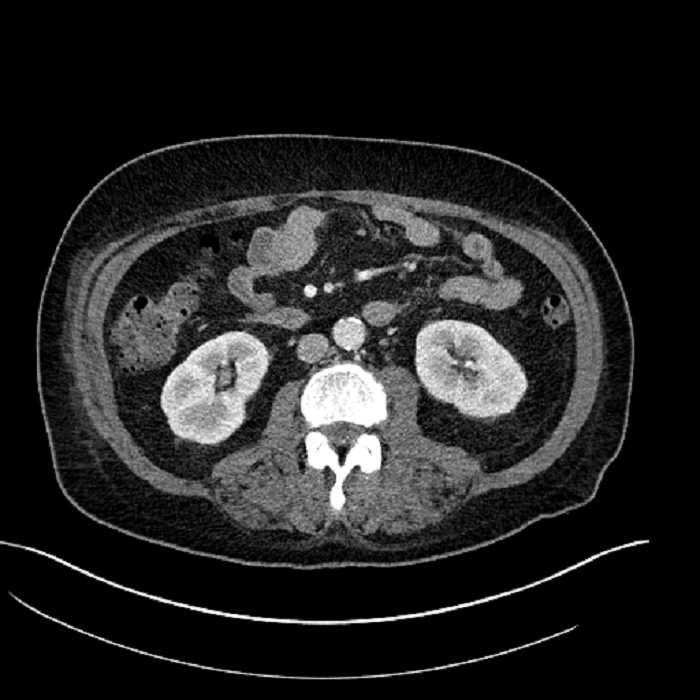

• Large fluid density structure in hepatic segments 7 and 8 measuring 10 x 7 x 7 cm with internal septation and circumferential ill-defined low density compatible with edema

• Peripherally enhancing subcapsular collections along the anterior margin of the left hepatic lobe measuring 3 x 1 cm and 2 x 1 cm

• Clearly marginated fluid density structure in segment 7 and several other scattered tiny hypodensities, which likely represent cysts

Acute sigmoid diverticulitis complicated by a small contained perforation and a large abscess in the right hepatic lobe. Additional small subcapsular abscesses along the anterior margin of the left hepatic lobe.

• The classic CT imaging appearance is a double target sign with internal low density surrounded by an internal enhancing rim (capsule) and a low density external rim (edema)

Hepatic abscess showing the double target sign with low density internally surrounded by a thin inner enhancing rim (red arrow) and ill-defined outer low density rim (yellow arrow). Blue arrow indicates an internal septation. Red arrows: additional smaller subcapsular abscesses. Red arrow: focal contained perforation associated with diverticulitis.